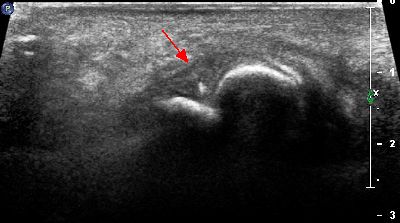

Microavulsione falange distale primo dito (img. 01) microavulsione falange distale primo dito 01

Microavulsione falange distale primo dito (img. 02) microavulsione falange distale primo dito 02